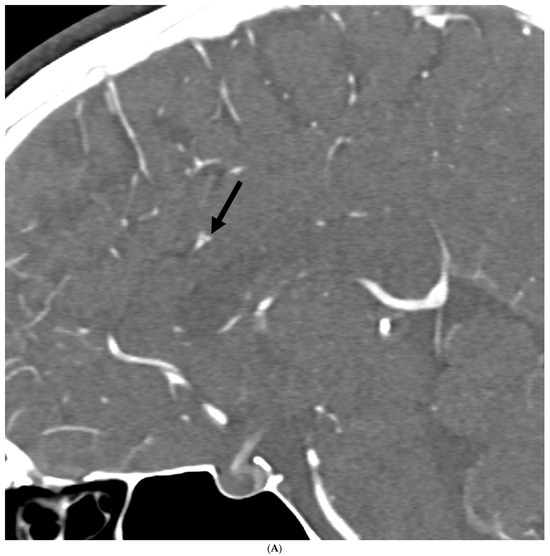

Prevalence of Intracranial and Cervical Artery Abnormalities in Patients with Hypermobile Ehlers–Danlos Syndrome and Hypermobility Spectrum Disorders Presenting to an Academic Headache Clinic

by Todd D. Rozen, Katelyn A. Bruno, Ethan M. Rozen, Frances C. Wilson, Marysia S. Tweet, Raymond C. Shields, Sharonne N. Hayes, Dacre R. T. Knight, Shilpa N. Gajarawala, Sukhwinder J. S. Sandhu, Alok A. Bhatt and DeLisa Fairweather

Neurol. Int. 2026, 18(2), 33; https://doi.org/10.3390/neurolint18020033 - 11 Feb 2026

Background/Objective: It remains unknown whether patients with the more common forms of hypermobility carry an elevated risk for the development of intracranial/cervical artery abnormalities. The objective of this study was to determine the prevalence of unruptured intracranial aneurysms, spontaneous cervical artery dissections, and fibromuscular dysplasia in patients with hypermobile Ehlers–Danlos Syndrome (hEDS) and hypermobility spectrum disorders (HSD) who presented to an academic headache clinic. Methods: This is a retrospective cohort study. We used an electronic medical record to look for all patients seen at the Mayo Clinic Florida Headache Center and EDS Clinic between 2019 and 2025 with a diagnosis of hEDS or HSD and neuroimaging of both the intracranial and cervical arteries. Results: There were 103 patients who met the inclusion criteria. There was no statistically significant difference between hEDS and HSD patients in developing cerebral/cervical arterial anomalies. Of the sample, 95% of the hypermobile patients with abnormal neuroimaging also had migraine. A total of eleven (10.7%) patients (hEDS + HSD) were diagnosed with unruptured intracranial aneurysms. Trends included age less than 50 years, small aneurysms in the anterior circulation, and having migraine with aura. Five (4.8%) patients were diagnosed with spontaneous cervical artery dissection with trends for HSD, over the age of 50 years, vertebral artery involvement and a history of migraine without aura. Six (5.8%) patients were diagnosed with fibromuscular dysplasia with trends for HSD, over the age of 50 years, carotid artery involvement and a history of migraine with aura. Conclusions: This is the first study to identify that patients with the more common type of EDS, HSD and hEDS, and a possible concomitant history of migraine have a heightened risk for the development of unruptured intracranial aneurysms, spontaneous cervical artery dissections, and fibromuscular dysplasia. Our findings suggest the need for targeted screening with intracranial and extracranial arterial imaging for this unique patient population. Full article

Figure 1